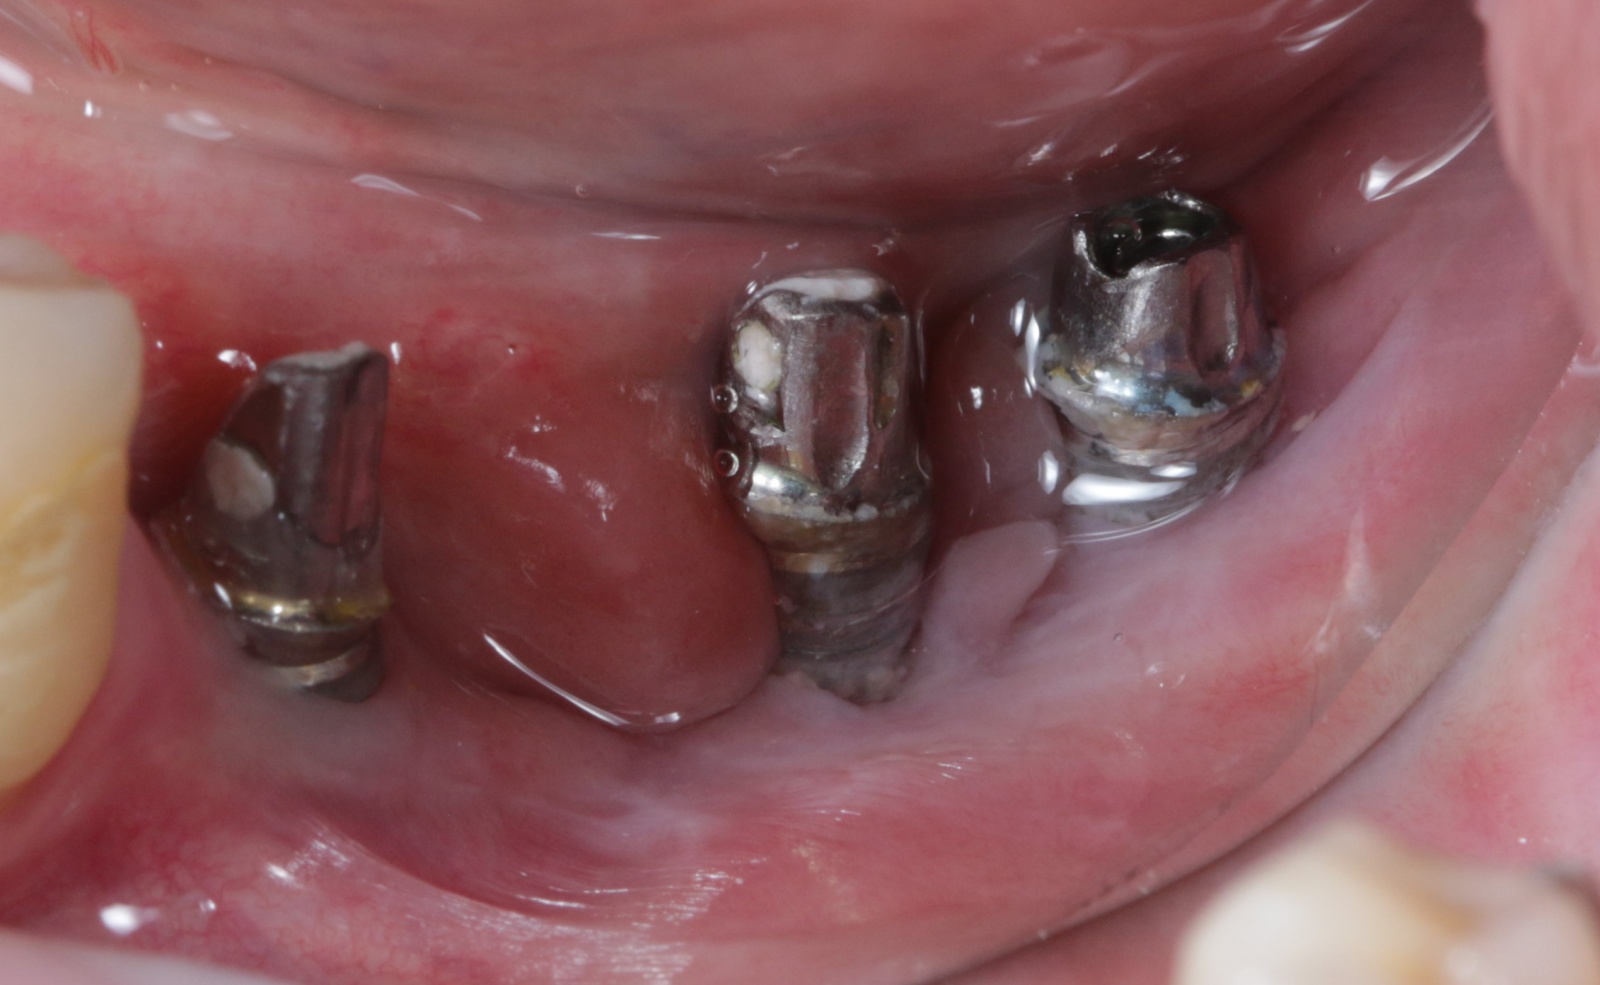

Пациент обратился в клинику с жалобами на забивание пищи и периодические боли в области установленных коронок на нижней челюсти слева. После того, как наш ортопед их снял, сразу стало понятно, в чем же тут проблема.

Вот эти шматки и есть фиксирующий цемент. Почему это произошло? А все потому, что очень сложно вычистить его из-под десны полностью. В связи с чем возникают серьезные проблемы.

После снятия коронок в полости рта мы наблюдаем воспаленную гиперемированную десну.

Была произведена антисептическая обработка и установка формирователей десны. Фото ниже сделано на момент восстановления.